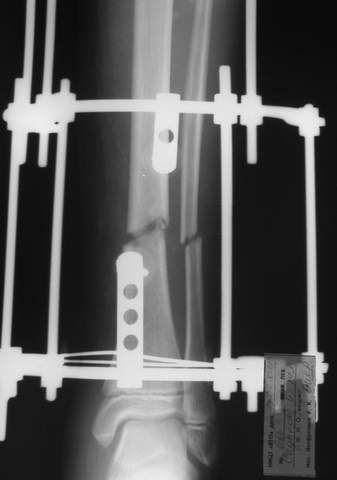

В аттачтах №№ 1 и 2 - примеры, когда 2 кольца не позволили послеоперационно

исправить смещение фрагментов большеберцовой (по ширине и вальгусное).

А казалось бы (#2) - поиграй на штангах и все влетит.

1

1a